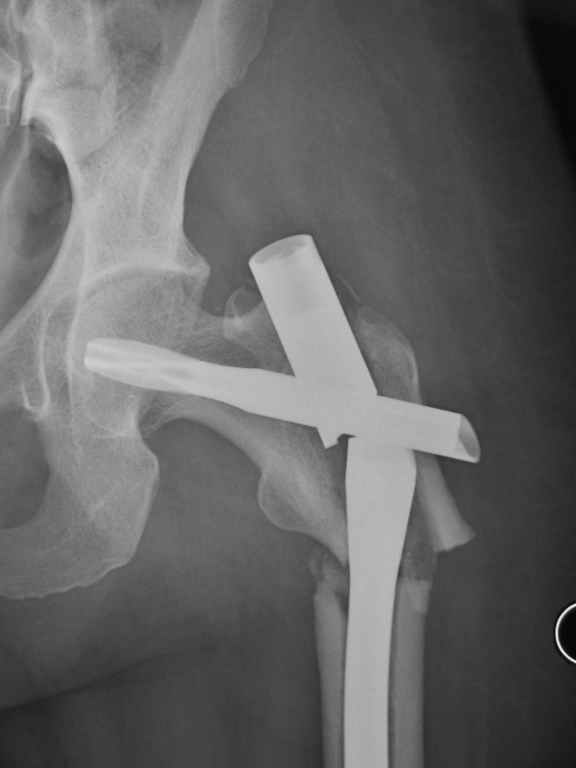

I was wondering if you could give me your thoughts on a case. 50 yo female with breast cancer who had pathologic fracture of proximal femur. Originally fixed with PFN which has broken.

Tough case. It should have healed, I think it was the right implant.

Was it in varus to start? Too much stripping w/ the reduction?; or poor protoplasm and cancer. On the lateral it looks like the piriformis starting point was reamed w/ starting point too posterior and aiming too ant. and med. This is a common problem w/ this fx and the proximal piece ends up

flexed, ER and in varus. This may have contributed to failure, but this deformity will be the same challenge on the revision. Do you have